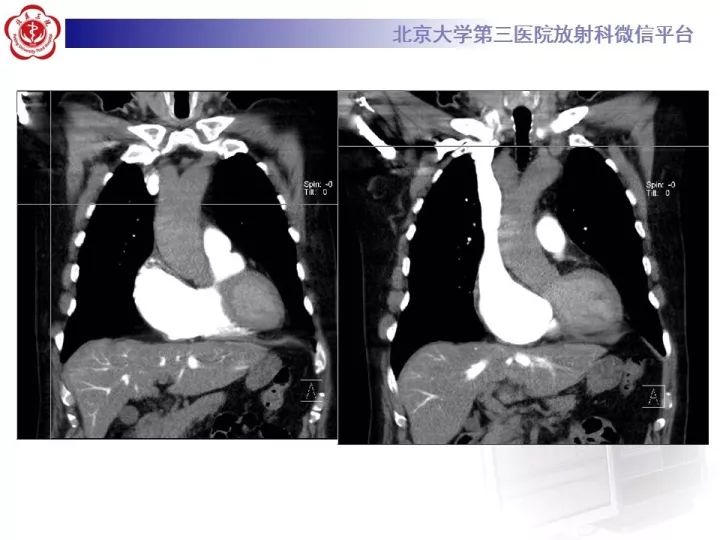

【病例】双主动脉弓畸形1例CT